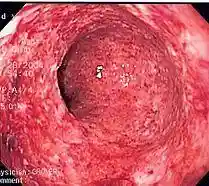

![]()

Colitis (inflammation of the colon) caused by Crohn's Disease.